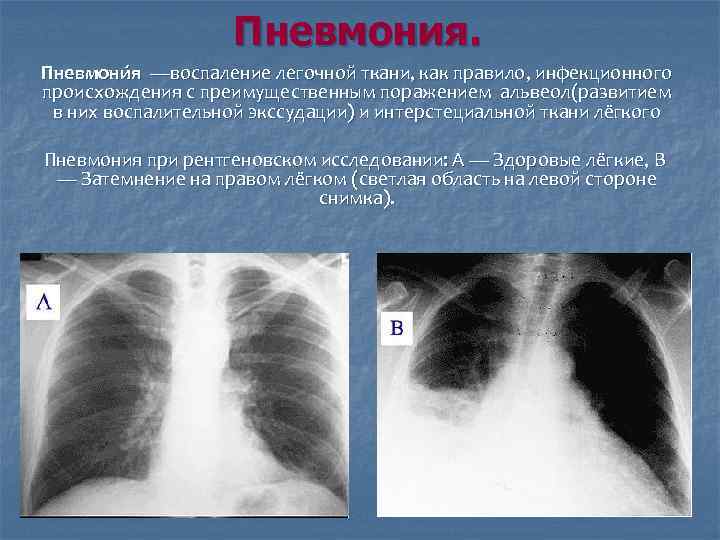

Рентгенодиагностика бронхопневмонии: Советы и примеры